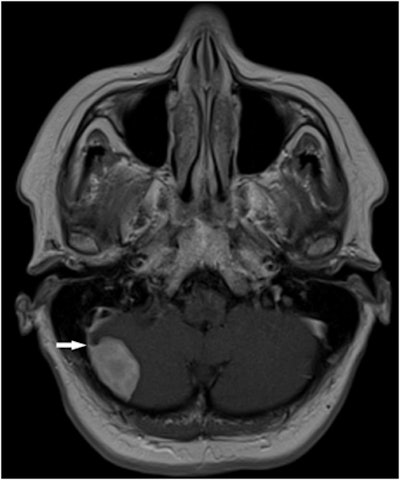

Type III findings included one brain glioma, one bronchogenic carcinoma, one renal cell carcinoma, one complicated renal cyst, one ovarian tumor, one testicular Leydig cell tumor, and metastases to the lung, liver, and adrenal gland in one patient, Cieszanowski said. Benign lesions classified as type III included a meningioma.